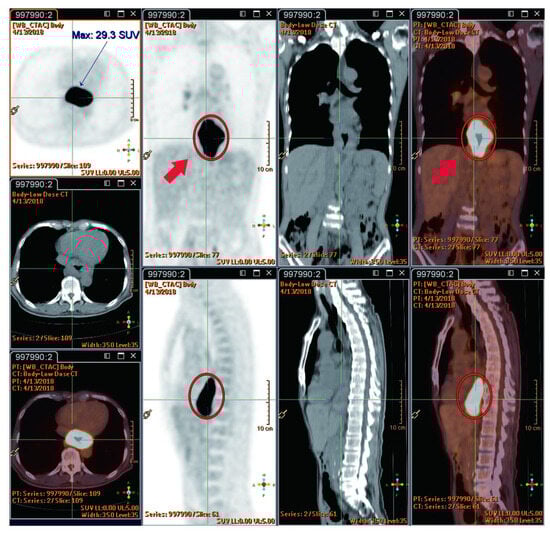

| 10 | Shai et al. (2020) [48] | M | 66 | Asian | Yes | 50 Gy | NA | No | T3N1M0 | 1 | 0 | 0 |